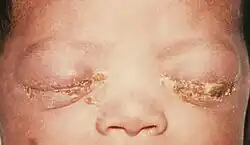

Kapavkový zánět spojivek u novorozenců

Těhotné matky infikované kapavkou mohou přenést nemoc na děti během porodu. Gonokoková konjunktivitida (zánět oční spojivky) je jedna z hlavních příčin slepoty u novorozenců. Lze jí předejít aplikací vhodných očních léků, které se nasazují při podezření na zvýšené riziko v tomto směru. Lékaři doporučují, aby se žena před porodem nechala vyšetřit na některé nemoci včetně kapavky.

Kapavka se nejčastěji šíří při pohlavním styku. Infikované ženy mohou též přenést kapavku na novorozence během porodu, což se nejčastěji projeví jako oční infekce. Tato komplikace se v ČR prakticky nevyskytuje, protože novorozenci narozeni v porodnici mají preventivně ošetřeny oči vkápnutím Opthalmo Septonexu.